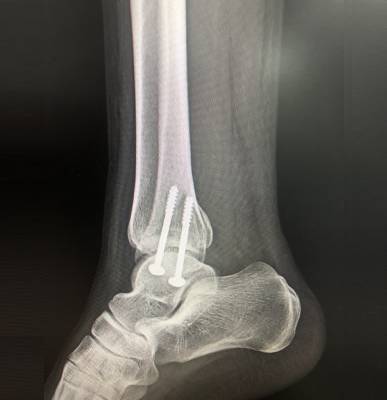

Dr. Haytham Elkhatib is a distinguished orthopaedic surgeon specializing in comprehensive musculoskeletal care. With expertise in trauma, fracture treatment, and advanced interventional joint injections, he offers innovative solutions for various conditions.

I had surgery with Dr. Haytham, and I’m very happy with the results. He previously operated on my leg after a fracture, and that surgery was very successful. Recently, I had another surgery on my knee, which was done in the simplest and most professional way. After the operation, I was able to return to my normal life — I can play football and be active again after a long time of not being able to. Dr. Haytham and his team took great care of me throughout the process, and I truly thank him for his excellent work and dedication